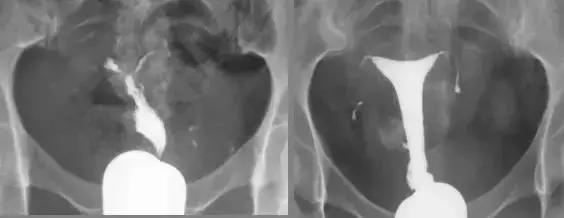

输卵管间质部阻塞

子宫结核 输卵管结核

输卵管积水